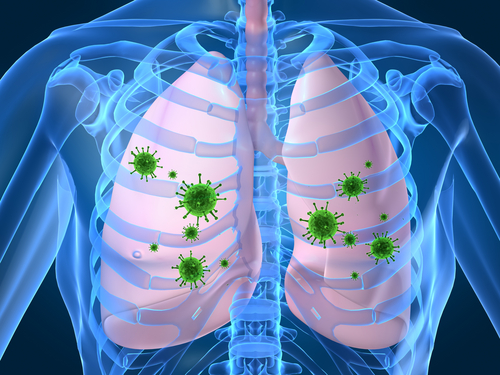

Pulmonologia este o ramură a medicinei dedicată diagnosticului și tratamentului bolilor plămânilor și ale căilor respiratorii. Pulmonolog este o specialitate terapeutică.

Pulmonologia include o gamă largă de boli, cum ar fi:

Cele mai frecvente simptome care pot însoţi boli pulmonare și ale tractului respirator sunt tuse, respirație șuierătoare în piept, dificultăți de respirație. Cu toate acestea, aceste simptome sunt nespecifice și pot indica alte afecțiuni.